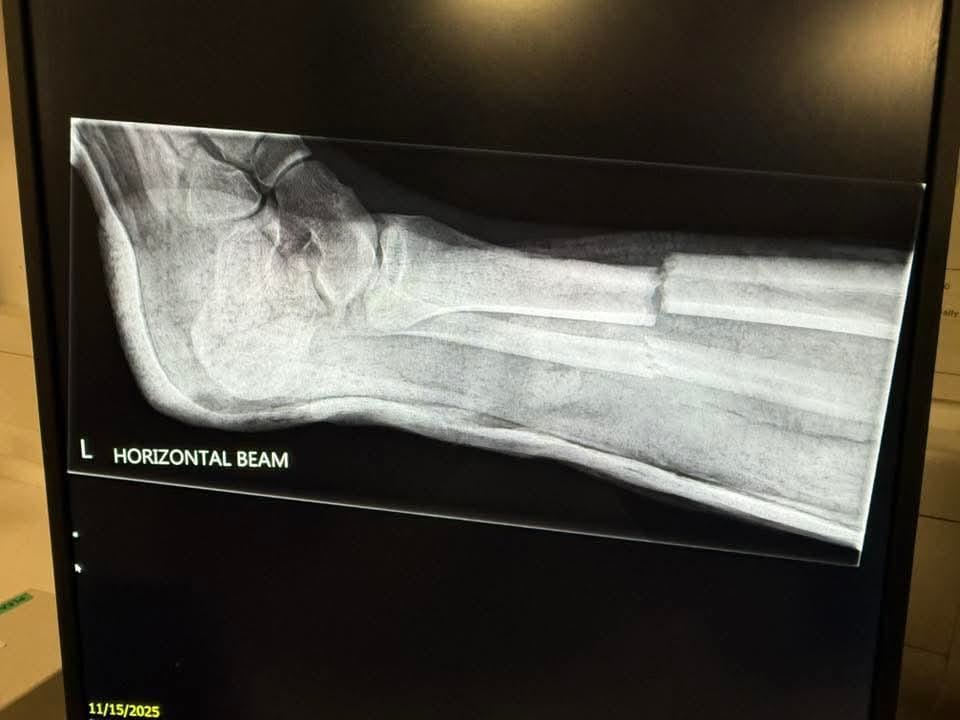

Below x-ray of the Ilfracombe player from abandoned game at Bridport @ilfcombeafc are campaigning to ban Micro Shin pads and @BudeFc & @DobwallsFC have said signed up SWP have written to @FA (awaiting reply) in meantime clubs asked to review policies regarding micro shin pads

swpleague's tweet image. Below x-ray of the Ilfracombe player from abandoned game at Bridport

@ilfcombeafc are campaigning to ban Micro Shin pads and

@BudeFc & @DobwallsFC have said signed up

SWP have written to @FA (awaiting reply) in meantime clubs asked to review policies regarding micro shin pads